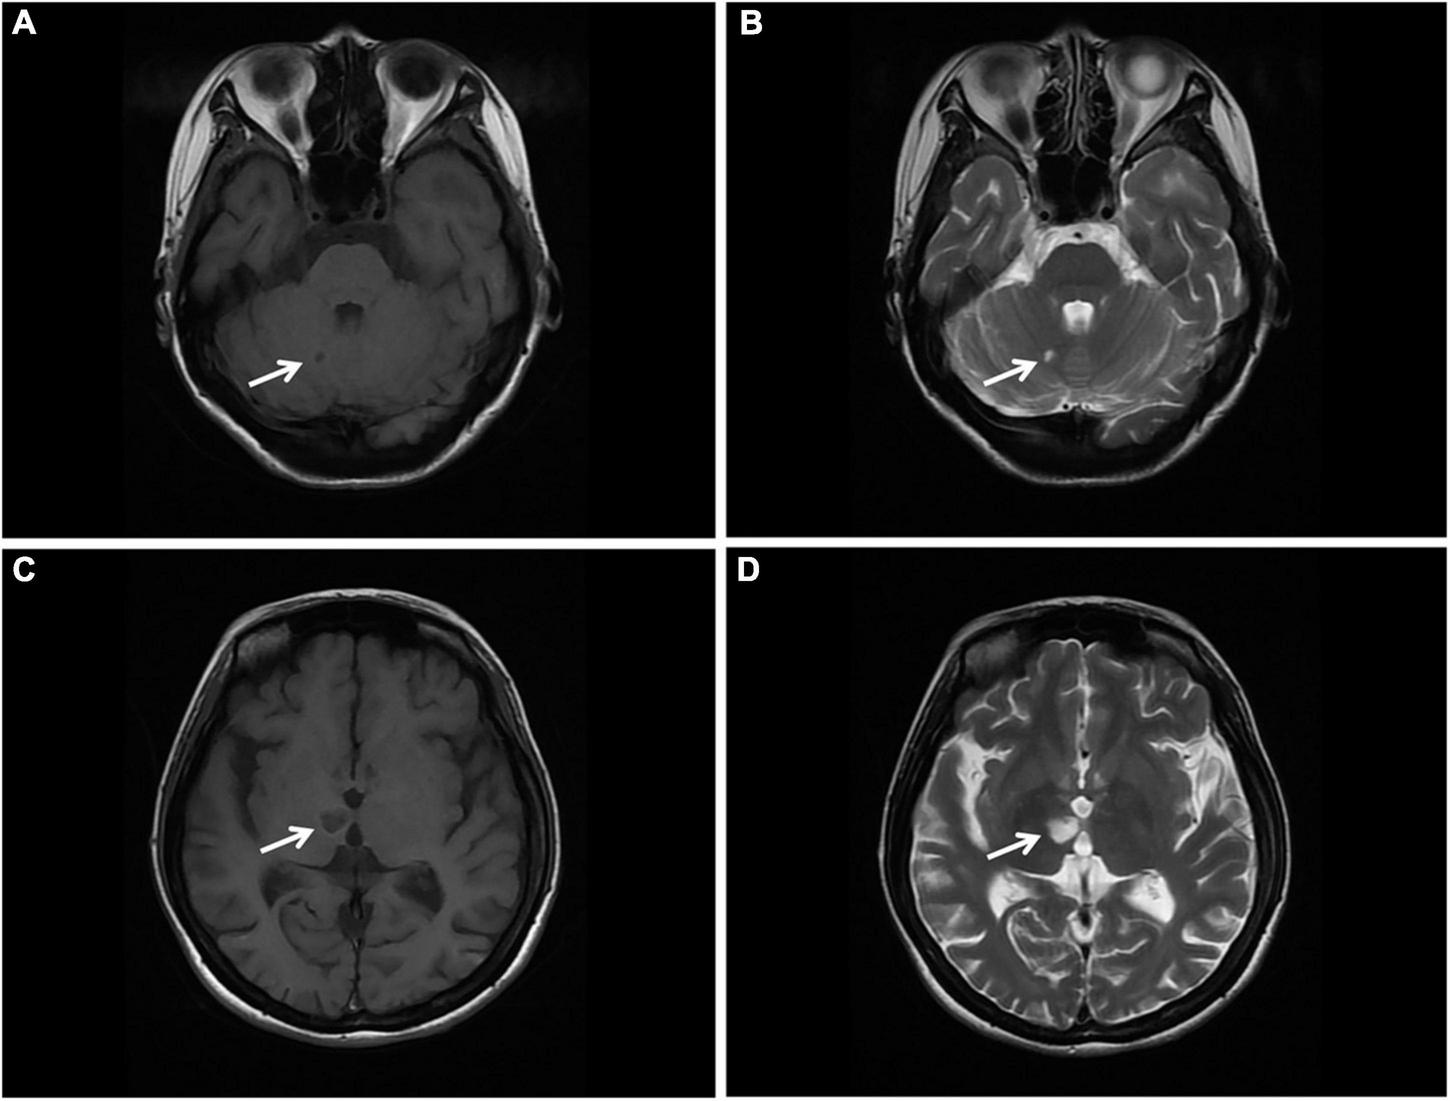

Magnetic resonance imaging (MRI) of the brain was then performed, showing multiple infarctions and softening lesions in the right thalamus, paraventricular area, and cerebellar hemisphere (Figure 1). Magnetic resonance arteriography (MRA) showed right middle cerebral artery occlusion. A carotid ultrasound scan was normal. Transthoracic echocardiogram (TTE) demonstrated that the cusps of the anterior and posterior mitral valve leaflets were thickened. Additionally, verrucous and nodular vegetations with heterogeneous echo-density could be seen at the commissural border of both mitral valve leaflets (Figures 2A,C). The vegetations were firmly attached to the surface of the valve without obvious independent motion. Mild to moderate mitral regurgitation was detected at the central commissure when the valve closed (Figures 2B,D) with an effective regurgitant orifice area (EROA) of 0.25 cm2 and the regurgitant volume of 36 mL. The other valves were morphologically normal. The left ventricular function was normal, with a left ventricular ejection fraction (LVEF) of 60%. Repeated blood cultures were negative, and the patient had no recent history of fever. Considering these findings, the patient was diagnosed with primary APS, LSE, and cerebral infarction. Symptomatic treatment was provided to her during hospital admission with sufficient low molecular weight heparin and warfarin anticoagulation. Oral prednisolone acetate (15 mg/day) and warfarin were administered after her discharge.

FIGURE 1

Brain MRI. (A,B) T1 and T2 sequences showing cerebral infarction with a clear border in the right cerebellar hemisphere (arrow). (C,D) T1 and T2 sequences showing cerebral infarction with a clear border in the right thalamus. MRI, magnetic resonance imaging (arrow).

Studies have also found that LSE might be a common and under-recognized pathological process of embolic cerebrovascular disease, a potential embolic source of cerebrovascular embolism in patients with SLE and APS, and an independent risk factor of cerebrovascular events (8, 14, 15). Cerebrovascular events in patients with APS may be caused by the fragmentation of LSE or may be related to the hypercoagulable state caused by antiphospholipid antibodies (8). Erdozain et al. have shown that cerebrovascular events are more prevalent in patients with significant valvular lesions (15). In the present case report, the MRI scan exhibited small, multiple and scattered cerebral infarctions, while the MRA showed occlusion of the right middle cerebral artery. The cerebral vascular event of this patient was considered to be attributed to the combination of arterial embolism due to hypercoagulability and cardiogenic embolism as a result of LSE.